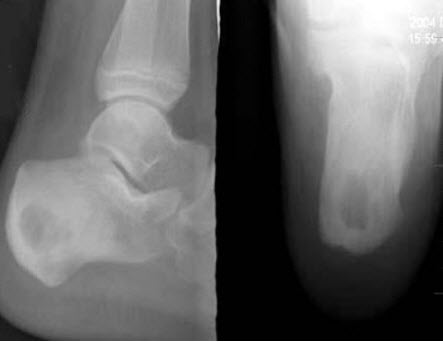

258、单项选择题

男,13岁,右跟骨疼痛不适3周,右跟骨侧、轴位摄片如图示,最可能的诊断是()

A.右跟骨结核

B.右跟骨骨囊肿

C.右跟骨骨巨细胞瘤

D.右跟骨血管瘤

E.以上均不正确